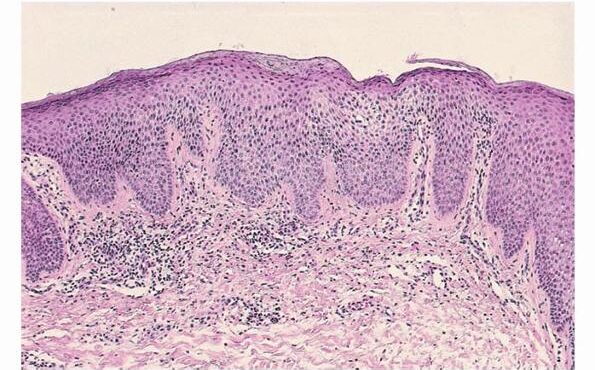

Nummular Dermatitis = التهاب الجلد المدنر= الاكزيمة المدنرة Nummular Dermatitis In nummular dermatitis, the eruption is characterized by pruritic, coin-shaped (nummular), erythematous, scaly, crusted plaques. The lesions tend to develop on the extensor surfaces of the extremities. Histopathology. Nummular dermatitis is the prototype of subacute spongiotic dermatitis . There is mild to moderate spongiosis, usually without […]